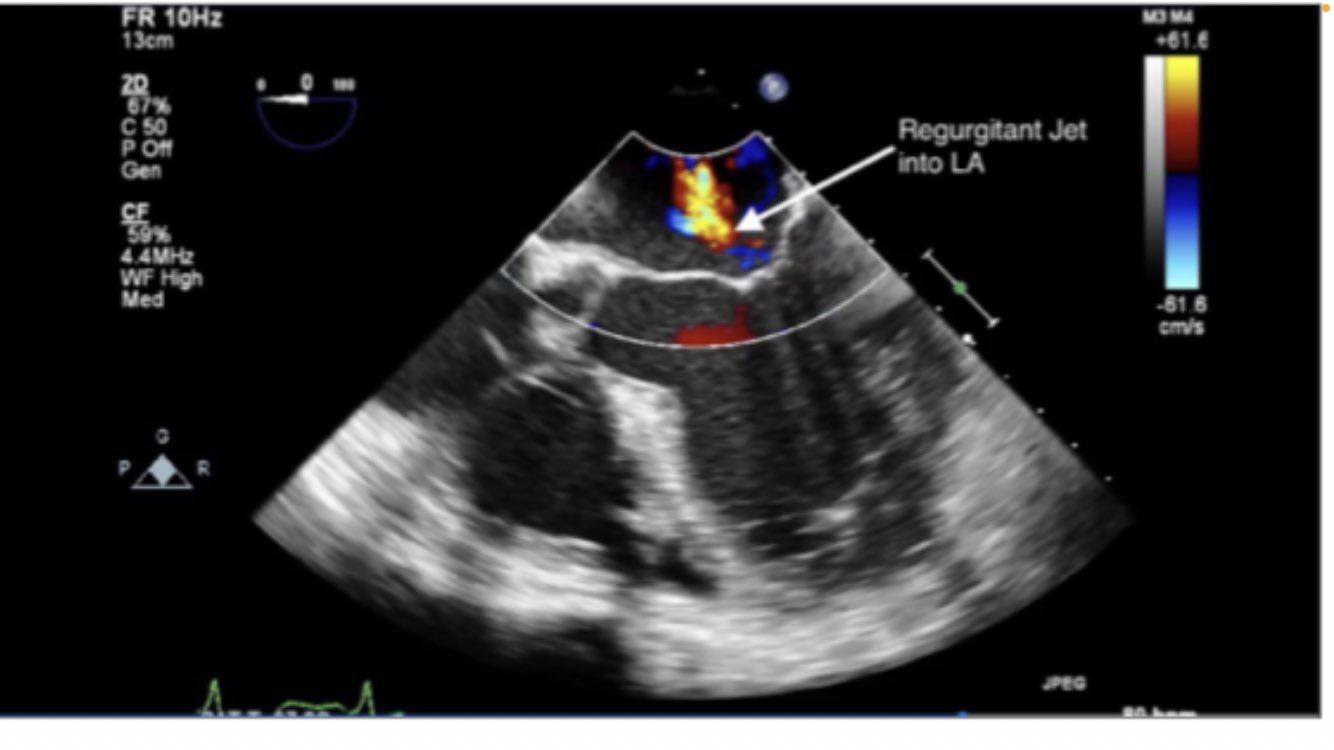

descending aortic SAX and LAX

DISSECTION

NO DISSECTION